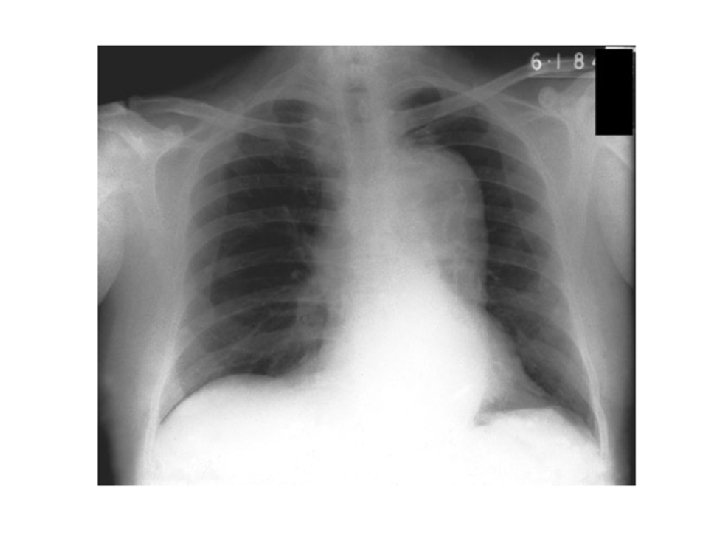

Pleural Effusion • • • Obliteration of the costophrenic angle Obliteration of the cardiophrenic angle Tracheal deviation Meniscus sign Compensatory hyperinflation Causes : heart failure, nephrotic syndrome, cirrhosis, pneumonia, tuberculosis, mesothelioma, bronchogenic CA, SLE, trauma.